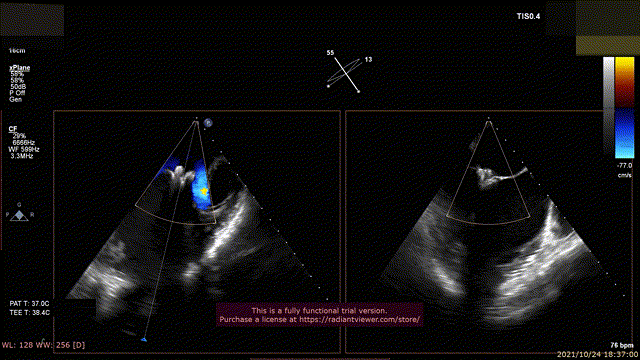

59岁男性,诊断重度功能性二尖瓣反流,二尖瓣重度反流4+(视频2),合并冠心病,严重慢性阻塞性肺部疾病,心脏功能III-IV级,多次测量EF 25- 30%,左心室舒张末期内径70mm。